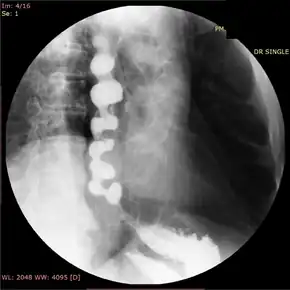

Barium esophagogram showed a constricted and curling of the esophageal lumen resembling a corkscrew.[15]

In people who have dysphagia, testing may first be done to exclude an anatomical cause of dysphagia, such as distortion of the anatomy of the esophagus. This usually includes visualization of the esophagus with an endoscope, and can also include barium swallow X-rays of the esophagus. Endoscopy is typically normal in patients with nutcracker esophagus; however, abnormalities associated with gastroesophageal reflux disease, or GERD, which associates with nutcracker esophagus, may be seen.[16] Barium swallow in nutcracker esophagus is also typically normal,[6] but may provide a definitive diagnosis if contrast is given in tablet or granule form. Studies on endoscopic ultrasound show slight trends toward thickening of the muscularis propria of the esophagus in nutcracker esophagus, but this is not useful in making the diagnosis.[17]